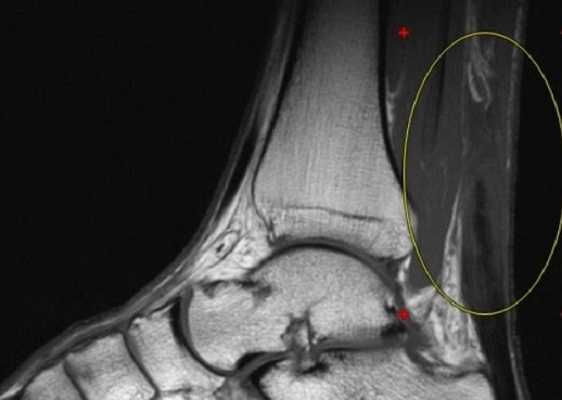

МРТ голеностопного сустава в сагиттальной плоскости. Отмечается полный разрыв пяточного сухожилия с признаками повреждения паратенона, реактивного паратендинита.

МРТ голеностопного сустава в корональной плоскости.

Отмечается поперечный стресс-перелом дистальных отделов малоберцовой кости.